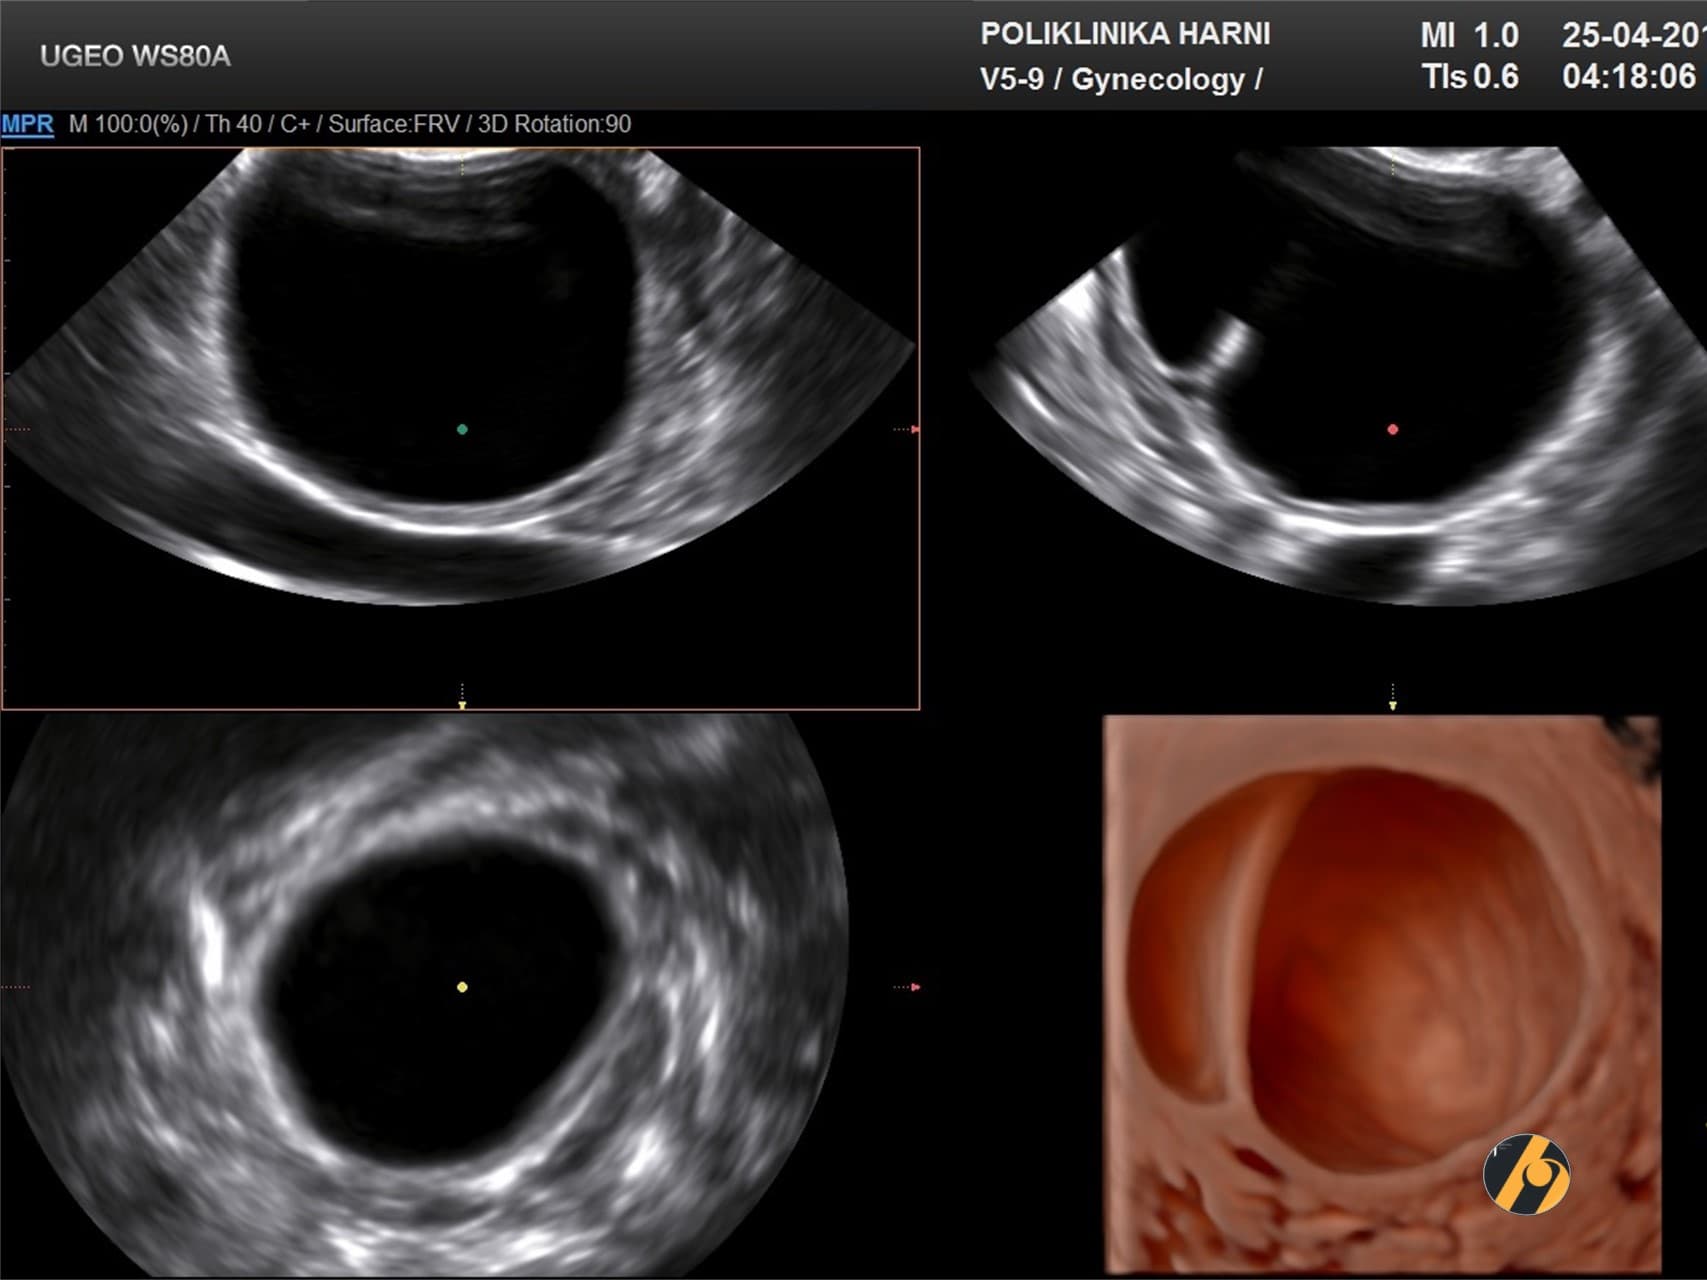

Na ultrazvučnom pregledu je ova cista unilokularna (sastoji se samo iz jedne šupljine), stijenka je tanka, a unutrašnjost ciste je anehogena (na ultrazvučnoj slici crne boje, usljed apsorpcije ultrazvučnih valova). Obično se povlače same od sebe, i rijetko zahtijevaju operativni zahvat, najčešće samo ukoliko dođe do njihove torzije / uvrtanja oko peteljke (cistektomija, adneksektomija).